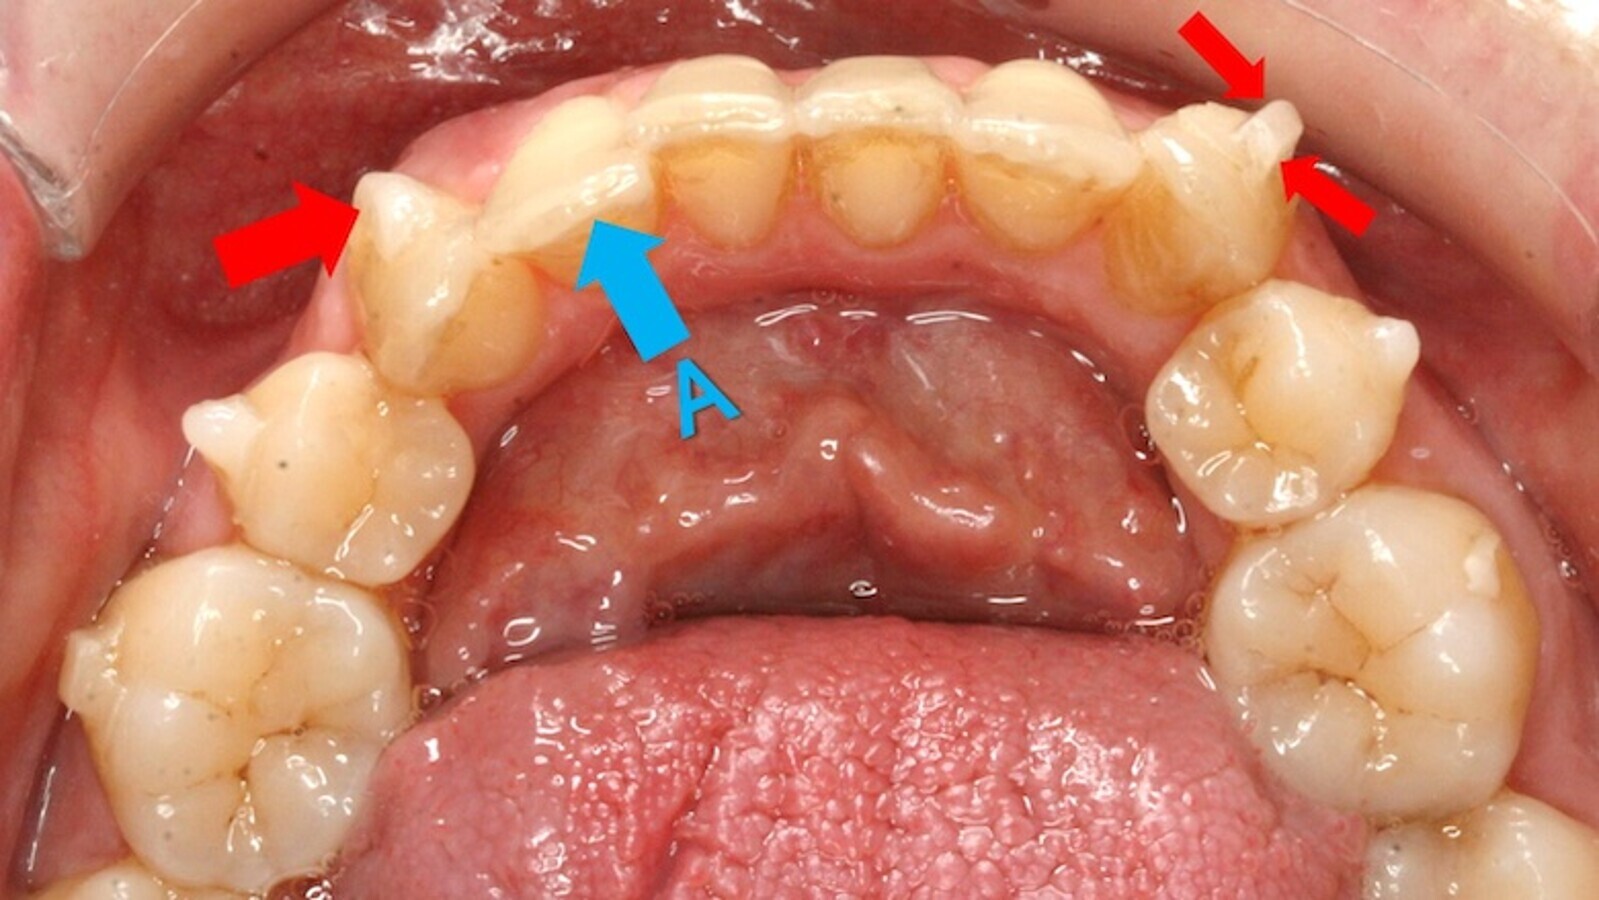

Por tanto, las fuerzas las va a ejercer el plástico sobre el diente desnudo (A) o a través de los ataches (figura 9).

Figura 9. Las fuerzas biomecánicas las ejerce el plástico sobre el diente desnudo (A) o a través de los ataches.